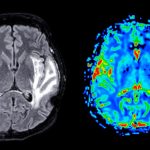

OMRF receives $2.6 million to study early effects of Alzheimer’s

Research will focus on stopping protein hyperactivity that precedes dementia